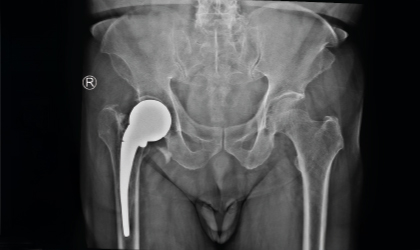

This 83 year old gentle man had a hip fracture 25 years ago. This became painful recently. He had an interesting (to the surgeons!) complication with a fracture of the stem in 3 places. This was revised to a total hip replacement. We used a longer stem to bypass the defects. He is mobile with a stick.

The patient’s old implant stem had fractured in three distinct places — a very rare and complex complication. This required careful planning for revision.